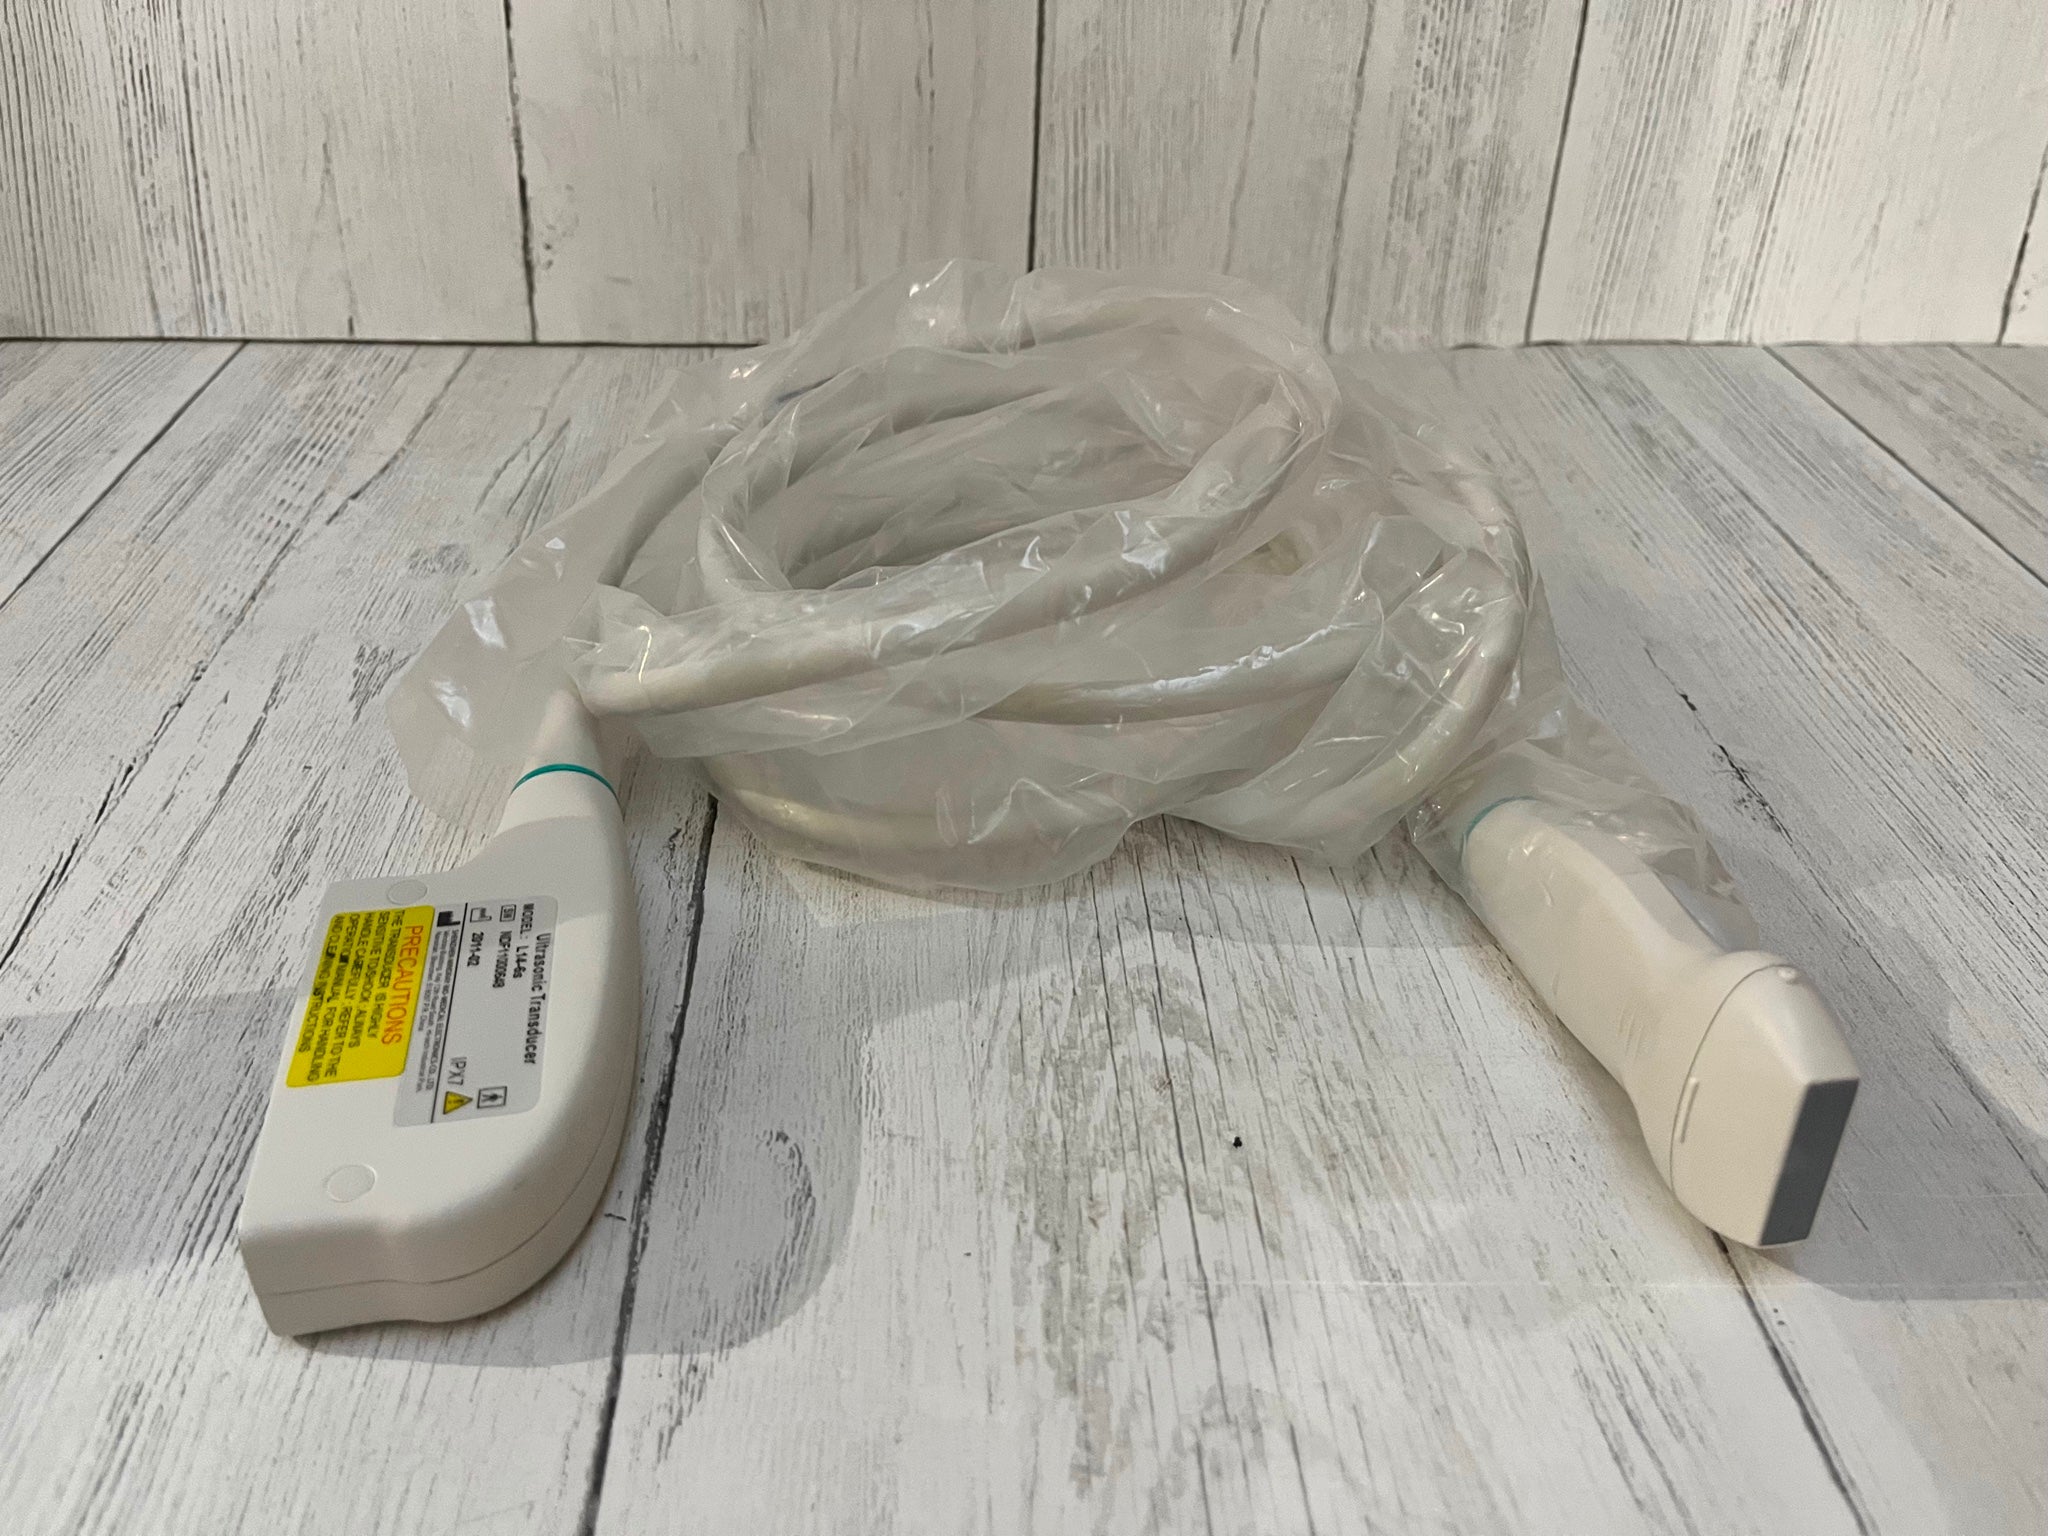

Save $ 1,619.82

DIAGNOSTIC ULTRASOUND MACHINES FOR SALE

SonoScape S2 with Convex Abdominal Probe Included - Excellent Condition

Sale price$ 7,379.18

Regular price$ 8,999.00